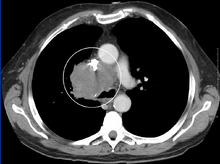

Approximately 90% of cases are associated with a cancerous tumor that is compressing the superior vena cava,[2] such as bronchogenic carcinoma including small cell and non-small cell lung carcinoma, Burkitt's lymphoma, lymphoblastic lymphomas, pre-T-cell lineage acute lymphoblastic leukemia (rare), and other acute leukemias.[2] Syphilis and tuberculosis have also been known to cause superior vena cava syndrome.[2] SVCS can be caused by invasion or compression by a pathological process or by thrombosis in the vein itself, although this latter is less common (approximately 35% due to the use of intravascular devices).[2]

The main techniques of diagnosing SVCS are with chest X-rays (CXR), CT scans, transbronchial needle aspiration at bronchoscopy and mediastinoscopy.[3] CXRs provide the ability to show mediastinal widening and may show the presenting primary cause of SVCS.[3] CT scans should be contrast enhanced and be taken on the neck, chest, lower abdomen and pelvis.[3] They may also show the underlying cause and the extent to which the disease has progressed.[3]